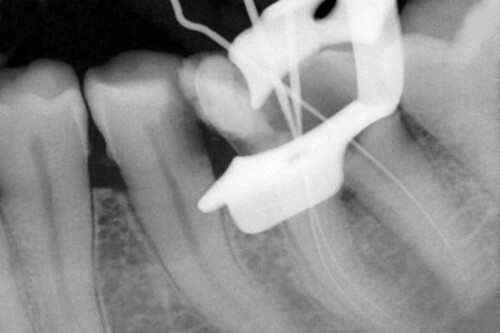

После введения местной анестезии, под изоляцией резиновой пломбой, отверстие доступа было изменено, и каналы были расположены. С помощью локатора апекса (Root ZX, J Morita, morita.com) рабочая длина была установлена на 1 мм короче рентгенографического апекса и подтверждена с помощью рентгенограммы (рис. 3).

Рис. 3